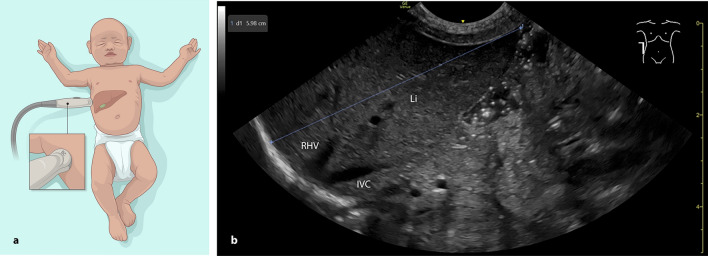

Purpose: In term and preterm infants, liver size is important for assessing growth and detecting conditions such as hepatomegaly, infections, or cardiac failure. The German Society for Ultrasound in Medicine (DEGUM) recommends measuring craniocaudal liver length in two frontal planes: the midsternal line (MSL) and the right anterior axillary line (AAL). This study evaluated whether liver length measurements in the right AAL from a lateral view yield results comparable to the standard frontal view, as the lateral approach may be technically more accessible and less stressful for neonates.

Material and methods: In this prospective single-center study conducted in a level III neonatal intensive care unit, 62 term and preterm infants underwent 107 liver measurements between July and December 2024. Each measurement was performed in both the frontal and the alternative lateral AAL plane. Statistical analysis included Wilcoxon matched-pairs signed rank test, Pearson Correlation Coefficient, and Bland-Altman analysis.